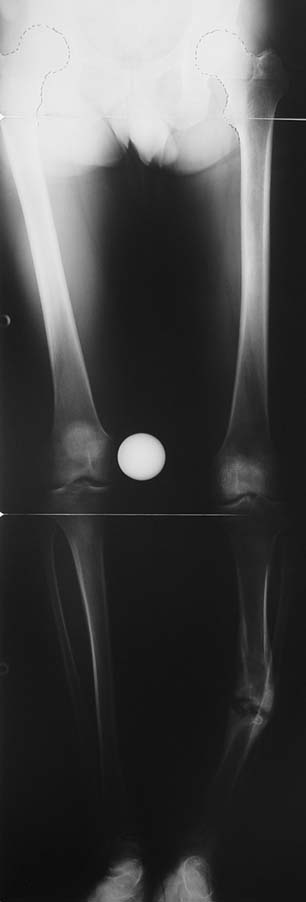

Appropriate radical debridement necessitates excision of all necrotic bone and soft tissues, and frequently causes instability at the involved extremity. The remaining bone and soft tissue defect has to be fixed and reconstructed. The distraction osteogenesis method of Ilizarov is used successfully for achievement of union, correction of the deformity, elimination of limb length inequality and reconstruction of segmental bone defects.

The duration of external fixation (external fixation index) depends on the amount of distraction required, and the extremity is prone to complications during this period. After the distraction phase is completed, the external fixator remains in place during the consolidation phase, which lasts twice as long as the distraction phase; but this period is hardly tolerated. If the external fixator is removed before sufficient consolidation is achieved, fractures, deformity and shortness will be the result. In our department, ‘lenghthening over nail’ method is used in order to decrease the external fixation index and increase patient comfort and activity level. In this method, the intramedullary nail is statically locked after the completion of the distraction phase, and external fixator is removed. The extremity is stabilized by the intramedullary nail during consolidation phase. In this way, complications due to long external fixation index or early removal of the external fixator are avoided.

Case 3